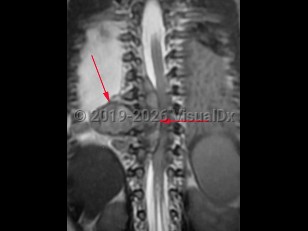

Neuroblastoma is a neuroendocrine tumor that arises from neural crest cells. It is the most common solid tumor of infancy and childhood; typical age of onset is less than 3 years old. The adrenal glands are the most frequent site of origin, but this tumor can be found anywhere along the sympathetic nervous system chain including the neck, chest, abdomen, or pelvis. Presenting symptoms depend on the site of origin and areas of metastasis if present but may be nonspecific including fatigue, fevers, anorexia, abdominal pain, or joint or bone pains. Less common symptoms include weakness, ataxia, chronic diarrhea, hypertension, or shortness of breath. The presence of Horner syndrome or opsoclonus-myoclonus syndrome in children should prompt evaluation for this type of tumor. Rarely, neuroblastoma may be an incidental finding on radiology.